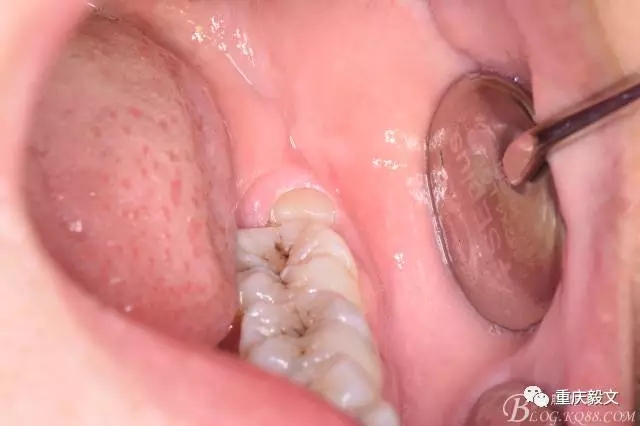

圖2.口內(nèi)可見(jiàn)黃豆大小大遠(yuǎn)中面暴露,擬采用潛掘法分牙,分別取出牙冠、牙根,達(dá)到真正的微創(chuàng)拔牙